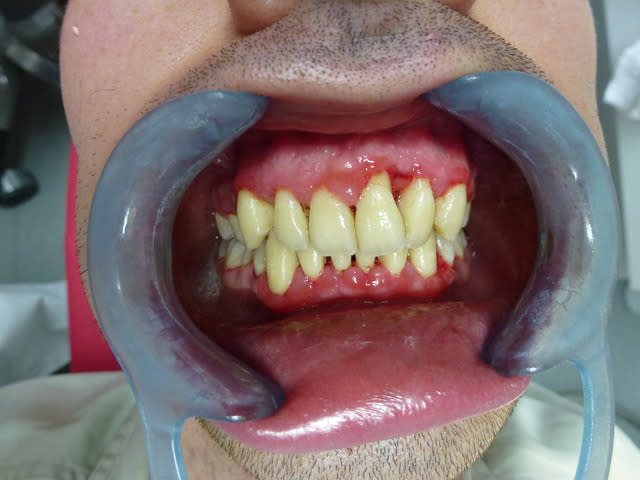

24 ans , propre sur lui, timide, très timide...

J'espère qu'il sera souriant sur sa photo de fin de traitement.

edit : septembre, octobre, novembre ouf!

je motive pour de l'odf...